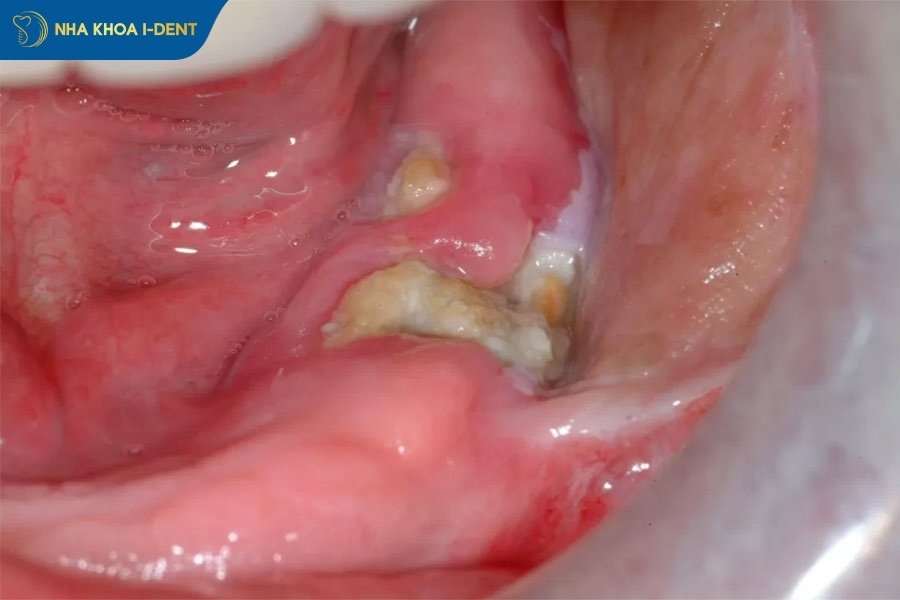

- Xương lộ ra trong ổ răng: Đây là dấu hiệu điển hình của viêm ổ răng khô, nơi xương hàm tiếp xúc trực tiếp với môi trường mà không có cục máu đông bảo vệ.